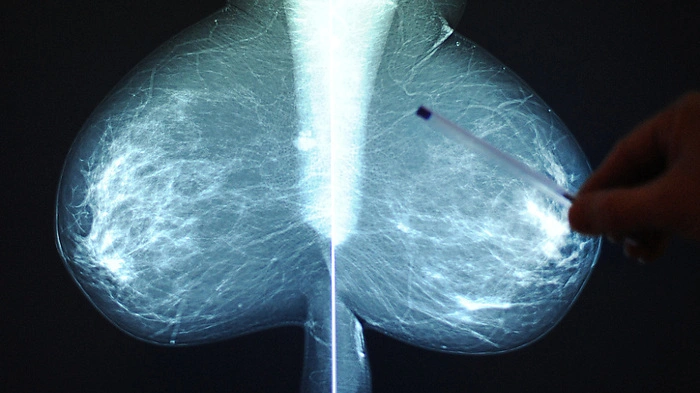

Das Röntgenbild gehörte zu einer anderen Patientin mit (fast) identem Namen (Symbolbild)

© APA/THEMENBILD